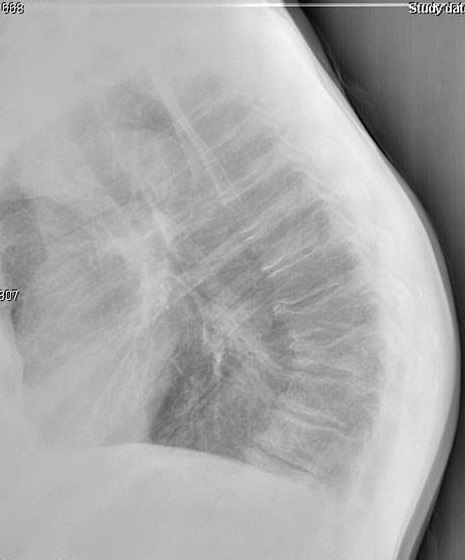

On figure 1, the original AP thoracic projection, an oval density is seen in the periphery of the right lung field (white arrow points to lesion). A thoracic and lumbar scoliosis is also seen. The lateral projection revealed multilevel degenerative change, as well as compression fractures at T9 and T10, with a focal kyphotic deformity seen in figure 2. Since a PA chest projection was not included, a chest series consisting of PA and lateral views was suggested to better evaluate the suspected lesion.